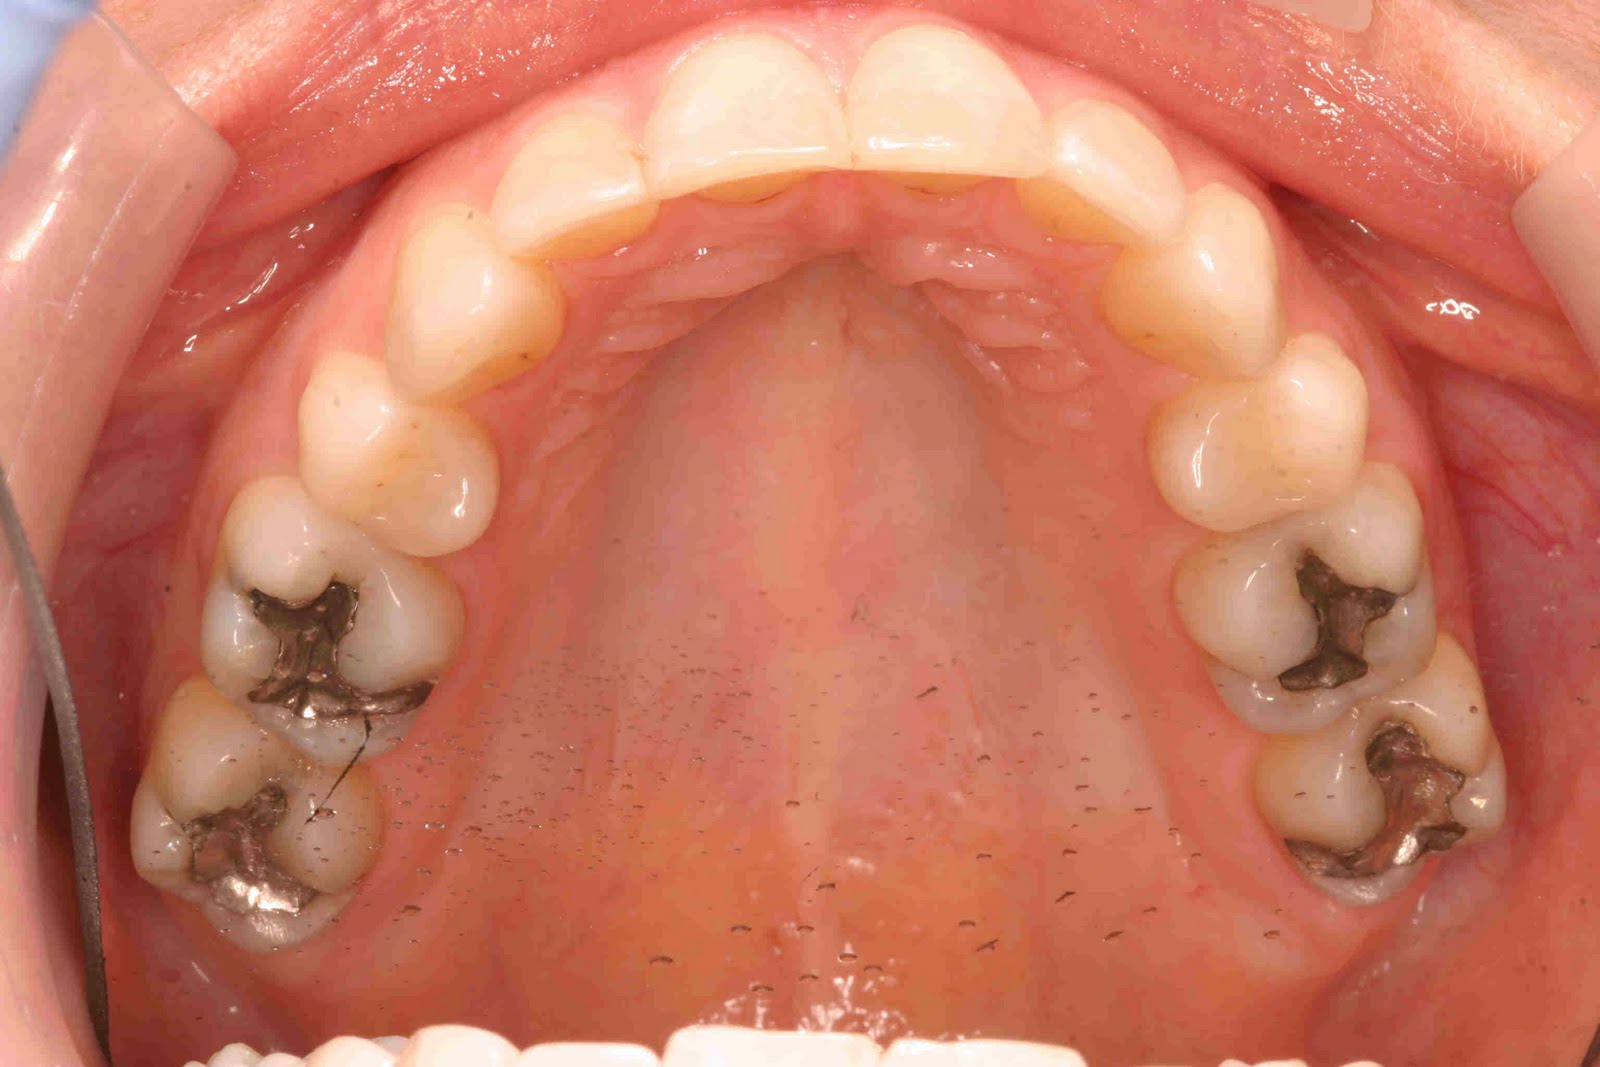

Replacing Silver Fillings with Toothcolored Dental Fillings Queens

Replacing Silver Fillings with Toothcolored Dental Fillings Queens Can A Dentist Replace A Filling At some point, you may need to consider replacing them. If that is the case, our dentist may recommend a replacement filling. A small filling may be replaced by a larger filling, the tooth might eventually need a crown and a root canal, and you could finally need to have the tooth taken out, says. However, each replacement gradually reduces. Can A Dentist Replace A Filling.

The beforeandafter of replacing silver fillings (amalgam) with white Can A Dentist Replace A Filling However, each replacement gradually reduces the amount of. First of all, don’t worry! Dental fillings are an essential part of maintaining oral health, especially when dealing with cavities and tooth decay. A temporary filling (described below) is placed to protect the tooth while the restoration is being made. Well, it’s mostly the same as a regular. If that is the. Can A Dentist Replace A Filling.